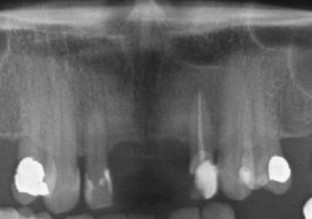

Fig. 1